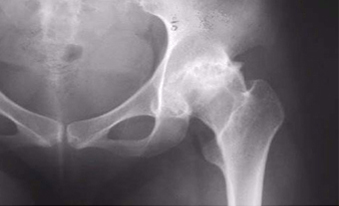

방사선(X-ray)사진 촬영 및 MRI촬영

초기에는 단순 방사선사진에 뚜렷한 변화가 관찰되지 않는 경우 MRI촬영이 필요합니다.

대퇴골두 무혈성 괴사 단순 방사선 사진